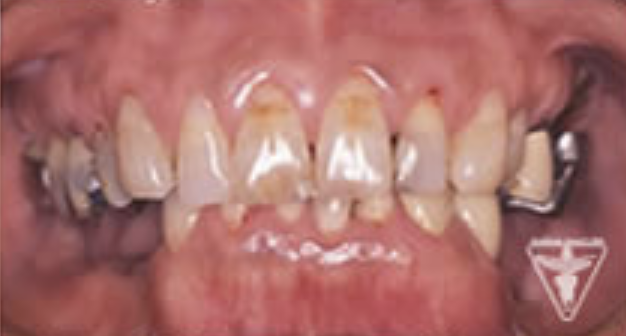

治療前

下の奥歯が左右なくなっており、かみ合わせが深くなっています。

顎のずれは認めませんが、歯肉が厚く中に炎症を取りこみやすいタイプの歯肉です。

左の顎の骨が大きく溶けてなくなっております。